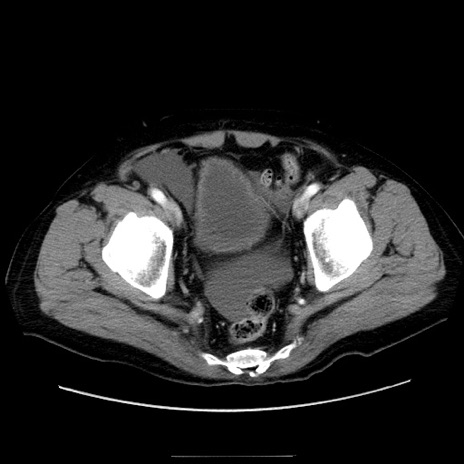

冠状断像

症例30(横断像)

【症例】80歳代男性

【主訴】臍周囲痛

【現病歴】約6時間前から臍下部痛が出現。次第に腹部膨隆・背部痛も生じてきたため来院。背部痛の場所は変化しない。

【身体所見】意識清明、BT 36.3℃、BP  131/87mmHg、P 87bpm、SpO2 100%(RA)、臍周囲自発痛・圧痛あり、反跳痛なし、自発痛部位に一致して板状硬あり、腹部膨隆、腸雑音減弱、CVA tenderness両側陰性。

【データ】WBC 19600、CRP 0.33